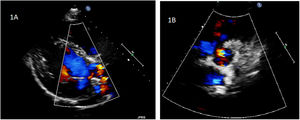

El seguimiento posterior mostró una paulatina dilatación de la neorraíz aórtica (NRA), un empeoramiento de la insuficiencia valvular, dilatación del ventrículo izquierdo y deterioro de la contractilidad ventricular. Con 10 años de edad y 30kg de peso, el último estudio ecocardiográfico mostraba una NRA de 20mm a nivel basal (z score: +2,56), 29mm a nivel de los senos de Valsalva (z score: +3,2) y 20mm a nivel de la unión sinotubular (z score: +1,8). El estudio mostraba una insuficiencia severa producida por 2 jets, uno excéntrico y otro central, el diámetro telediastólico del ventrículo izquierdo era de 48mm (z score: +1,9) y la contractilidad era del 45% (fig. 1 a y b). La ecocardiografía no mostraba segmentarismos y el estudio electrocardiográfico descartó lesiones indicativas de isquemia miocárdica. Dados estos hallazgos y la evolución de la paciente, se decidió una reintervención quirúrgica para reparar o sustituir la VNA.